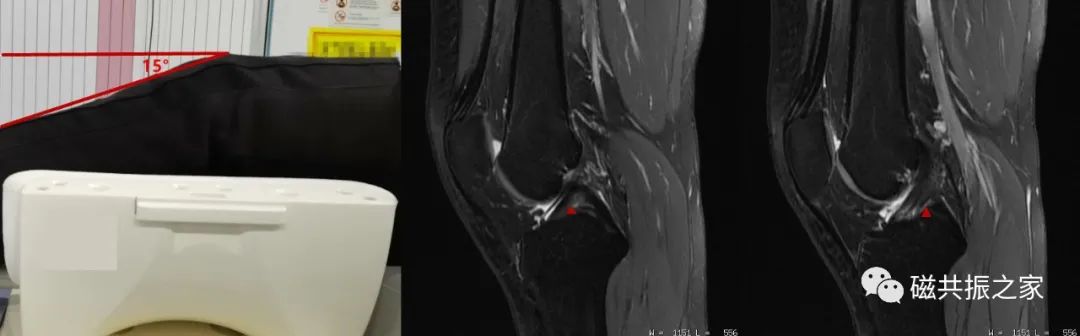

如临床扫描中通常会采用膝关节屈曲呈15-30°,使前交叉韧带更好的远离髁间窝上缘,从而让纤细的前交叉韧带能够完整、连续的在1-2层图像中显示,这样则更有利对前交叉韧带的评估,在临床中建议常规采用该体位扫描。

部分专用线圈其软垫会设计呈相应的屈曲角度,而大部分线圈的软垫未设计呈相应的曲度,对于这样的线圈则需要自行使用软垫使其膝关节屈曲呈临床需要的角度。

自行使用软垫使其膝关节呈屈曲状态时,应使用沙袋或软垫填充于线圈与组织间的间隙,以改善图像的均匀性。上图△,未使用填充物填充于线圈与组织间的间隙,从而获得的图像均匀度较差。

在膝关节的扫描中,合理使用沙袋不但可以改善图像质量,还可以有效的制动。